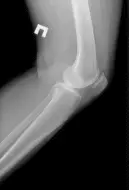

Картина, видима при рентгені коліна

Знімки робляться в двох проекціях: передньо-задній (прямий) і бічний. В першу чергу на рентгенограмі лікар-рентгенолог бачить анатомічна будова колінного суглоба

У процесі розшифровки рентгена колінного суглоба, лікар оцінює стан кісток, ширину суглобової щілини, наявність або відсутність остеофитов на бічних поверхнях стегнової і великогомілкової кісток, розташування і стан надколінка.

Рентген коліна при будь-якої травми, є основним методом дослідження для правильної постановки діагнозу. При переломах на знімках візуалізується стан кісток, пов’язане з травмою; наявність уламків, якщо стався перелом; пошкодження і зміщення надколінка.

Розширення або звуження суглобової щілини на рентгені колінного суглоба явно свідчить про артрит, артроз. Розростання кісткової тканини на бічних поверхнях кісток – так звані остеофіти.